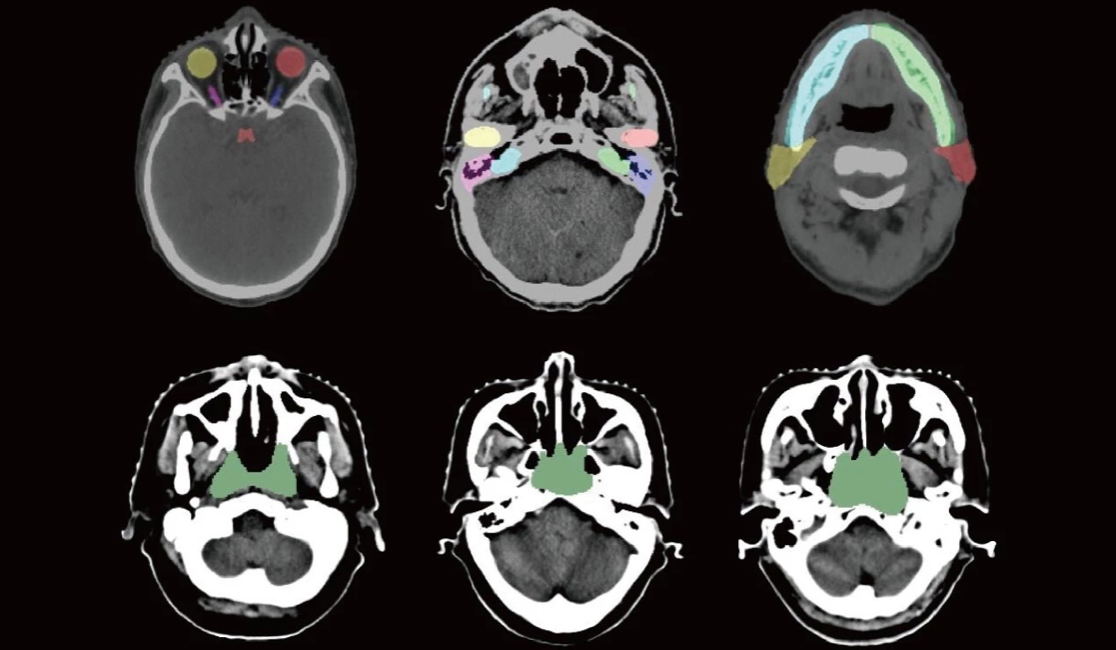

但业内普遍缺乏标准化高质量的训练数据,此次主办的MICCAI 2019放疗规划自动结构勾画国际挑战赛,将公布大量具有专家标注的CT数据,用于此次“头颈部危及器官(OAR)分割”、“胸部危及器官(OAR)分割”、“鼻咽癌放疗靶区(GTV)分割”和“肺癌放疗靶区(GTV)分割”四项挑战任务。这些CT数据包含鼻咽癌与肺癌两种癌症数据,且本次数据集规模比以往所有公开数据集规模都大,包含了50位鼻咽癌患者的CT数据及相应的1100个危及器官和放疗靶区GTV的标注,50位肺癌患者的CT数据及相应的300个危及器官和放疗靶区GTV的标注,这些数据集的释放,将极大地推动CT图像中危及器官和靶区勾画研究的进展。